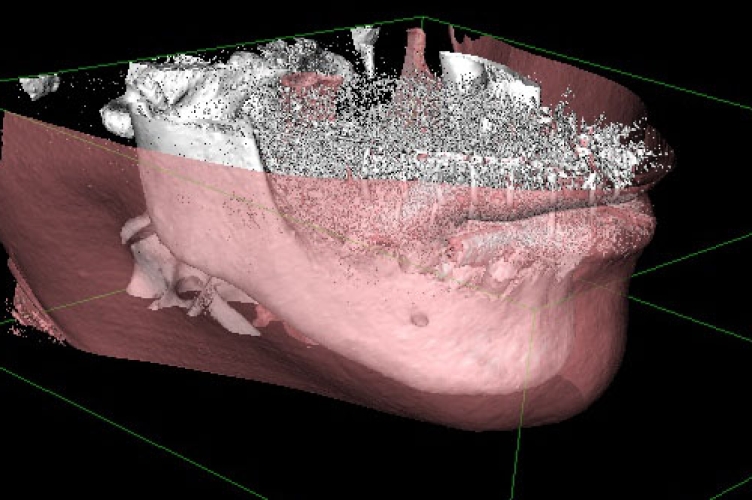

CT導入しました

インプラントとCT